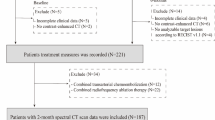

This retrospective study was approved by the local Institutional Review Board (ID: 2023-121), and the requirement for informed consent was waived due to the retrospective nature of the study. The study included 85 patients with confirmed CRLM from two hospitals, with data collected between January 2018 and March 2024. The inclusion criteria were as follows: (1) pathologically confirmed colorectal adenocarcinoma; (2) baseline hepatobiliary MRI and follow-up CT/MRI were acquired; (3) the diameter of measurable CRLM was larger than 1 cm; and (4) CRLMs were deemed unresectable at diagnosis. The exclusion criteria included: (1) the absence of the Response Evaluation Criteria in Solid Tumors (RECIST) evaluation; (2) presence of other tumors during the same period; and (3) poor quality of MR images. A total of 65 patients were enrolled from the hospital 1, while an additional 20 patients were included from the hospital 2. A flow diagram summarizing the study period and exclusion procedures is shown in Fig. 1.